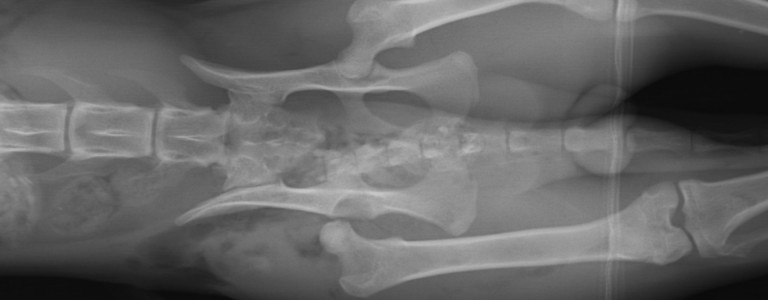

Diagnostic dysplasie

Le diagnostic repose sur un examen clinique et des radiographies pour évaluer l'état des articulations.

Le positionnement pour la radio de diagnostic est essentiel et est douloureux, cet examen se fait sous sédation.